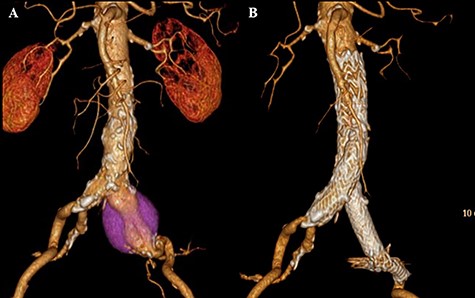

The patient recovered uneventfully, however, 1 year after open conversion, CT revealed a significant increase in the size of the unreplaced infrarenal aorta (Figs 3A, 4A and B). Reoperation was performed to treat the new aneurysm and on intraoperative findings, it was a true aneurysm. Abdominal aortic replacement was performed, however, infection of the vascular prosthesis occurred as a complication of this second open surgery. The infection was not controlled, and unfortunately, the patient died.

CT scan showing the significantly dilated infrarenal aorta, 1 year after open conversion (A, red arrow).